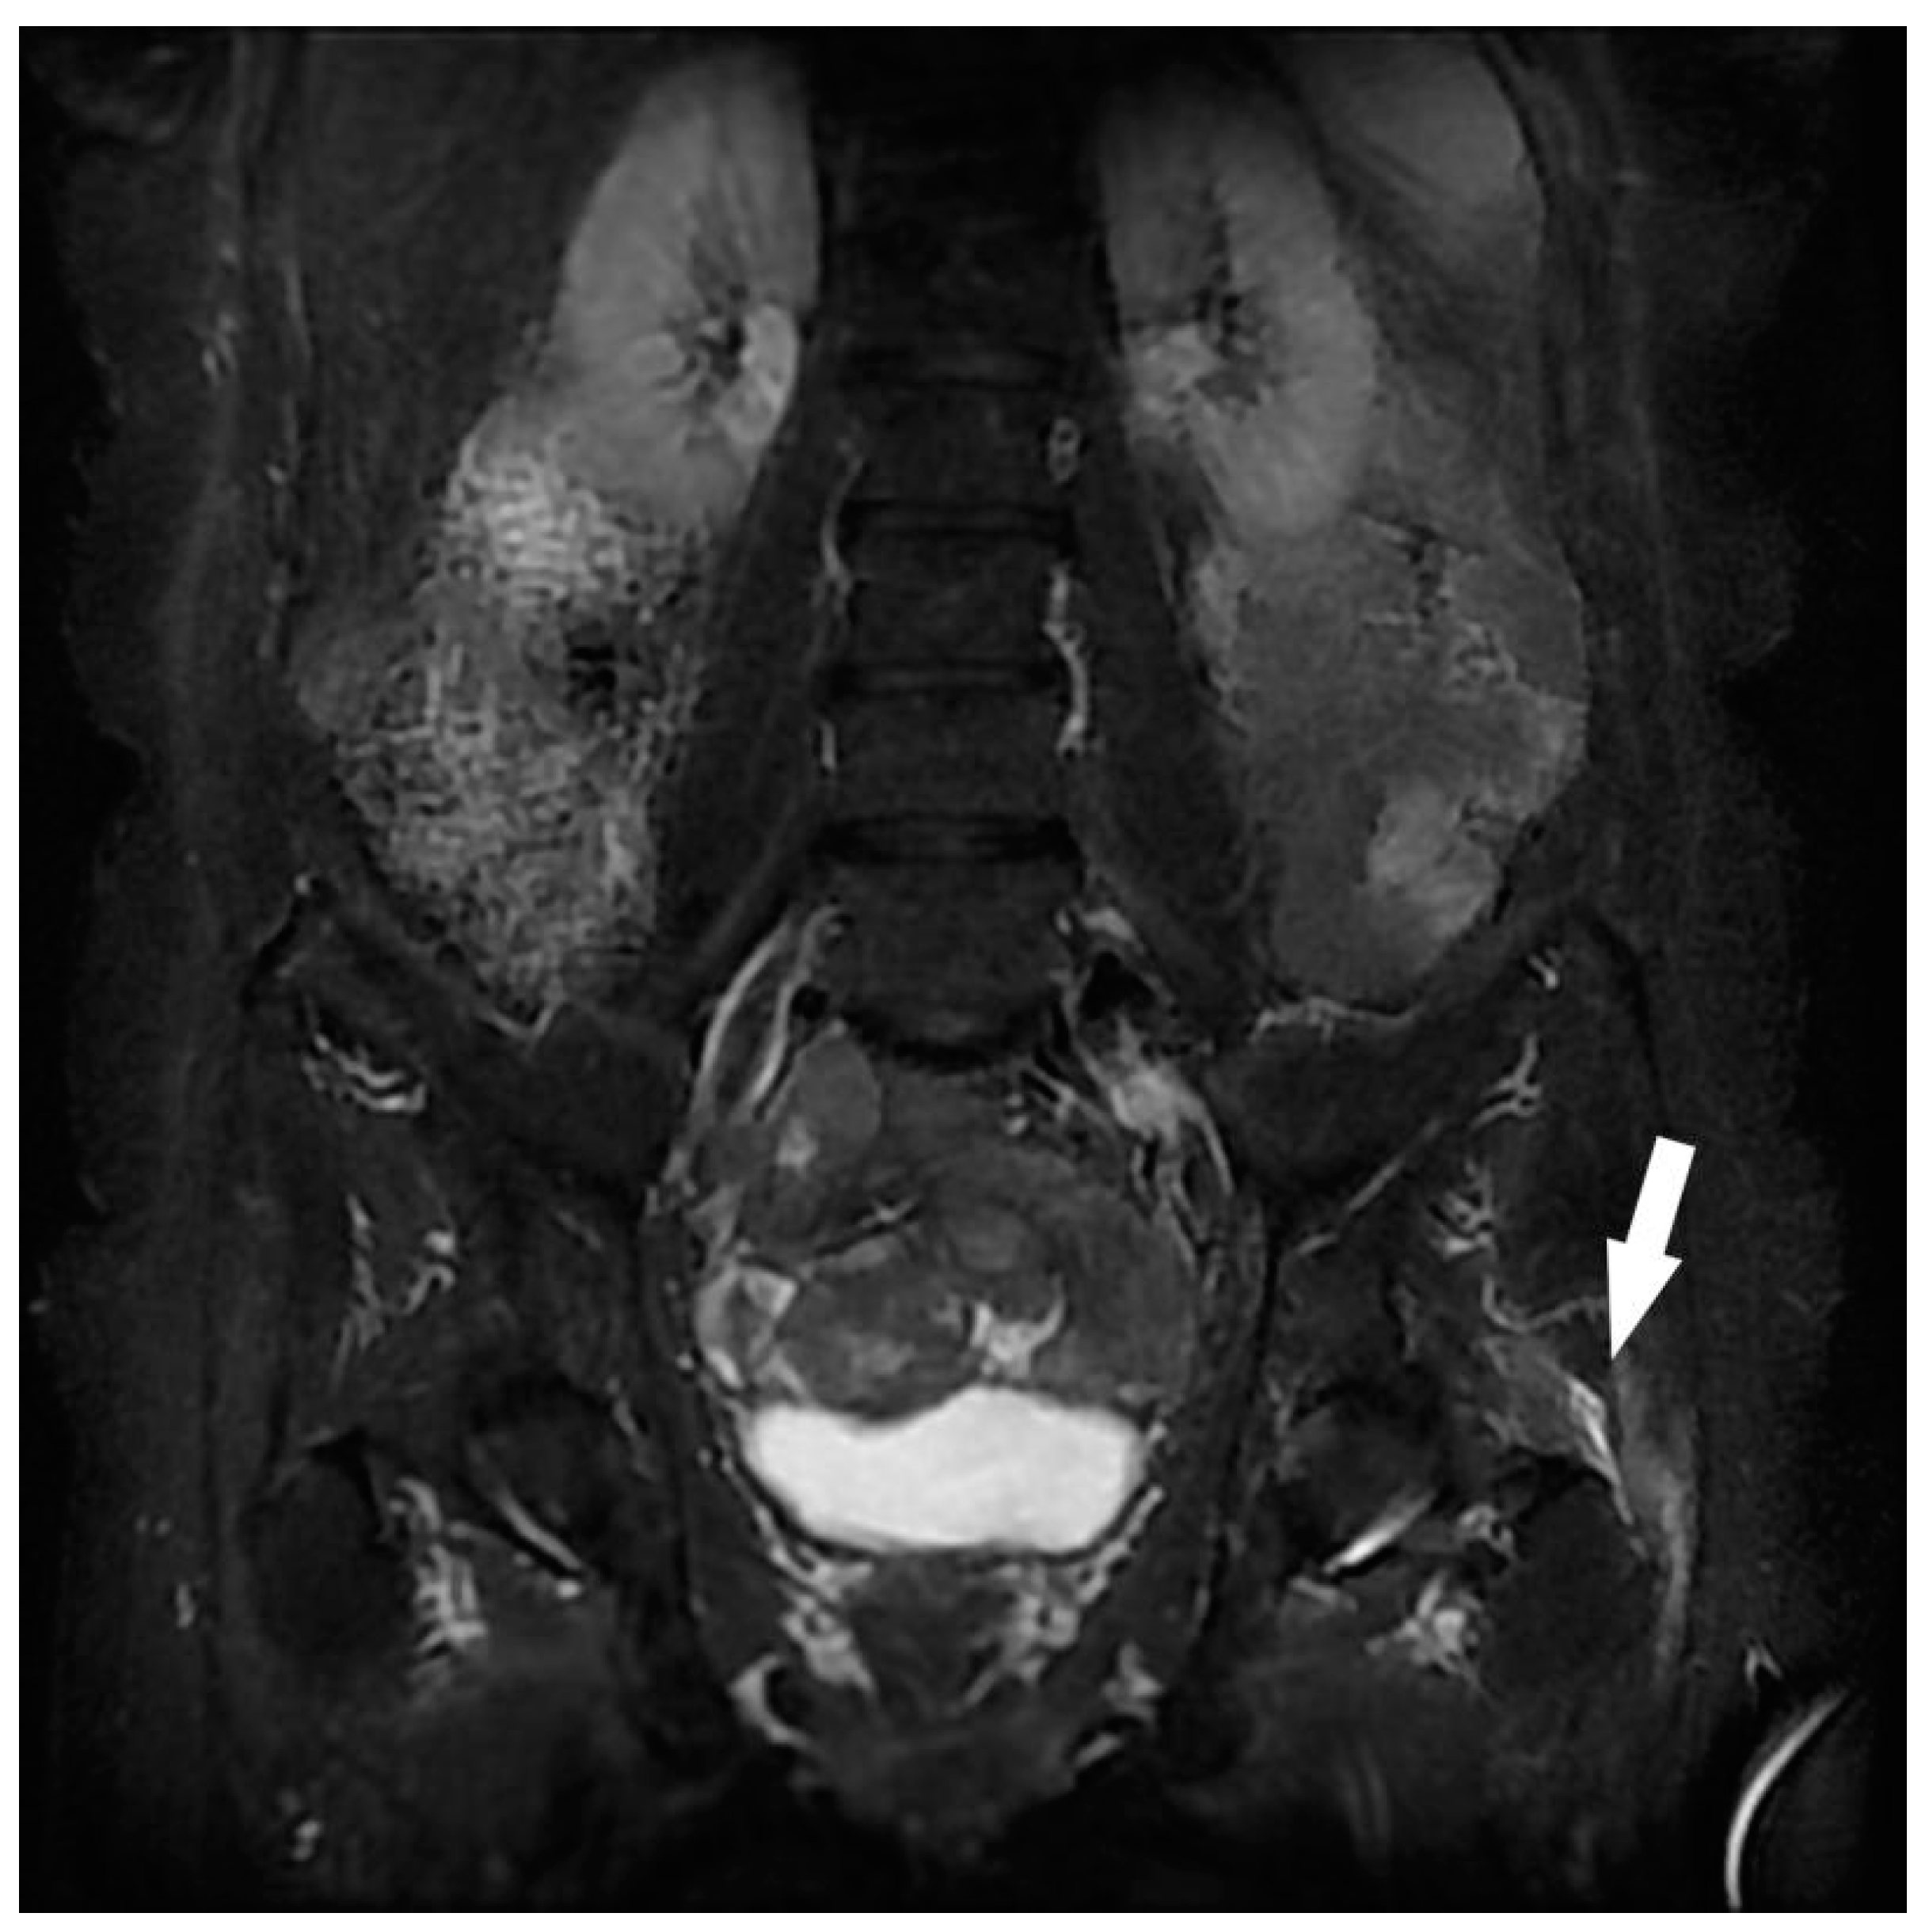

| Gluteal Muscles | Gluteal tendinobursitis | 21 |

| Sacroiliac Joint | Congestive degenerative arthropathy | 10 |

| Inflammatory sacroiliitis | 4 | |

| Sacral fracture | 1 | |